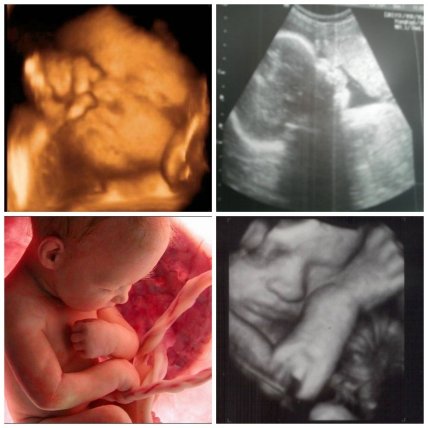

Начиная с 31 недели беременности, малыш будет прибавлять по 180-200 граммов в неделю. Сейчас его вес составляет 1400-1600 г., длина около 41 см., а диаметр головки почти 78 мм.

31 неделя беременности

31-я неделя беременности - изображение №1